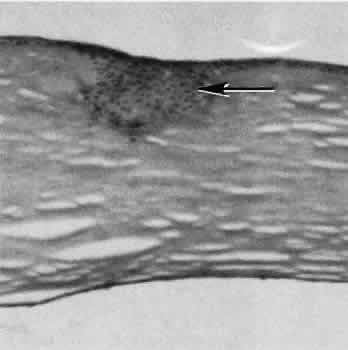

Fig. 5. Collagen lamellae retract when cut, causing the wound to gape when incised. If the extent of the incision is limited, as in clear cornea cataract incisions, the gaping may be countered by swelling of corneal stroma exposed to aqueous media. (Hematoxylin-eosin stain; × 100.)

Fig. 6. Descemet's membrane (D) has elastic properties that cause inward curling when incised. The fibrous reaction between cut ends of Descemet's membrane indicate a wound of long standing. (PD stain; × 100.)